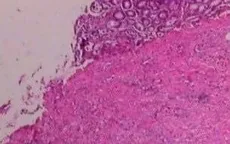

Nấm - kẻ giấu mặt nguy hiểm trong cơ thể người bệnh

VTV.vn - Không chỉ gây ngứa da hay nhiễm trùng thông thường, nấm có thể tấn công nội tạng, gây biến chứng nguy hiểm nếu không được phát hiện sớm và điều trị đúng hướng.